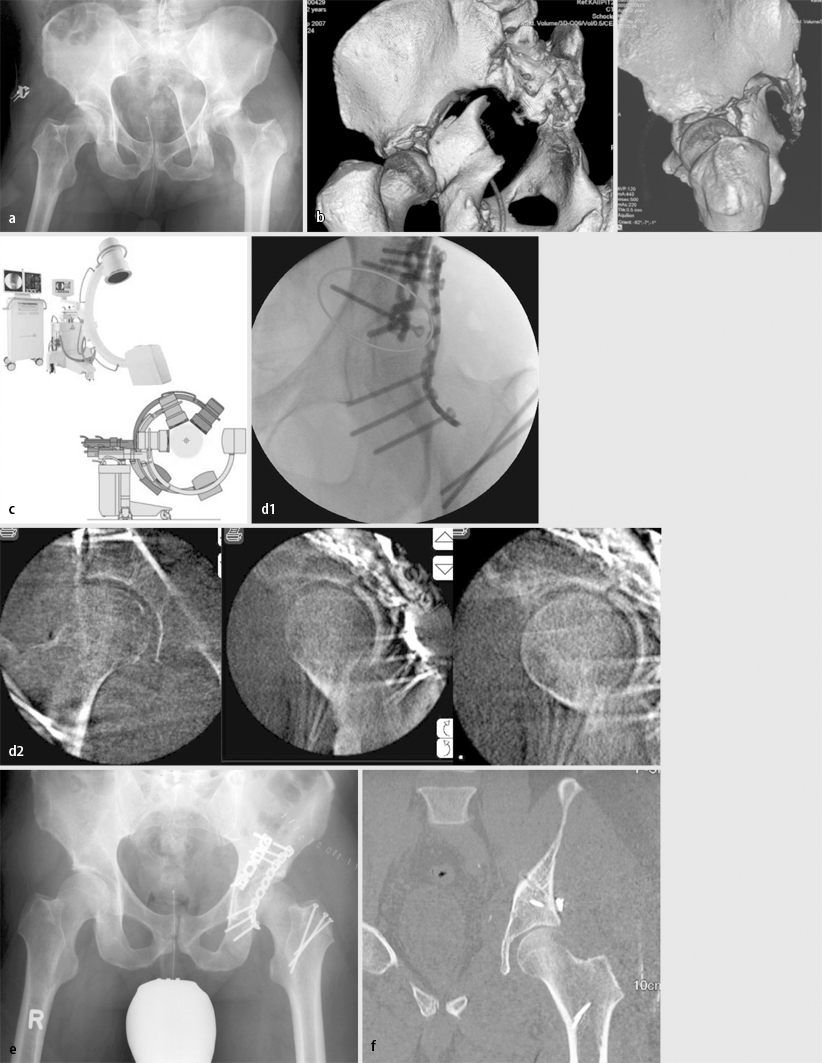

Fall 2, 21-Jähriger mit isolierter bilateraler transforaminaler Sakrumfraktur AO 61C3.3), a Outlet- und Inlet-Aufnahme, b 3D-Oberflächenrekonstruktion in analoger Projektion, c CT-Nativschnitt und sagittale 2D-Rekonstruktion, d volumenorientierte Rekonstruktion, e a.-p., Inlet- und Outlet-Aufnahme nach Versorgung mit triangulärer bilateraler spinopelviner Transfixation, weitere Erläuterungen s. Kasuistik

Fall 3, 24-Jähriger mit isolierter Beckenringverletzung AO 62C1.3, a unzureichende a.-p. Aufnahme des Beckens, b CT mit koronarer Rekonstruktion: C-Verletzung mit vertikalem Versatz, Abriss des Querfortsatzes von LWK5 rechts, mehrfragmentärer Stauchungsfraktur des Sakrums, c offene Reposition, weitere Erläuterungen s. Kasuistik

Fall 2

Bei dem 21 Jahre alten Mann lag eine isolierte bilaterale transforaminale Sakrumfraktur AO 61C3.3 („blow-out-fracture“) vor. Die Diagnose erfolgte mittels Outlet- und Inlet-Aufnahme, 3D-Oberflächenrekonstruktion in analoger Projektion, CT-Nativschnitt und sagittaler 2D-Rekonstruktion sowie volumenorientierter Rekonstruktion (Abb. 2 a–d).

Nach Reposition wurde die Verletzung mit triangulärer bilateraler spinopelviner Transfixation versorgt (Abb. 2 e).

Fall 3

Bei dem 24 Jahre alten männlichen Patienten war es bei einem Motorradunfall zu einer isolierten Beckenringverletzung (AO 62C1.3) gekommen. Die a.-p. Aufnahme des Beckens (Abb. 3 a) war lagerungs- und aufnahmetechnisch unzureichend. Die CT-Aufnahmen mit koronarer Rekonstruktion belegten eine C-Verletzung mit vertikalem Versatz sowie Abriss des Querfortsatzes von LWK5 rechts und eine mehrfragmentärer Stauchungsfraktur des Sakrums (Abb. 3 b).

Die Versorgung erfolgte durch offene Reposition der Sakrumfraktur mit winkelstabiler Platte und spinopelviner Transfixation bzw. supraazetabulärem Fixateur externe.